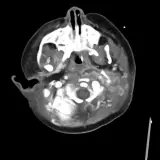

Over 2,100 interactive radiology cases, curated by radiologists for your level of training. Scroll, window, and view cases full screen — just like on PACS. Click linked findings in each writeup to jump straight to them on the image. Cases include sample reports, a focused discussion section, original illustrations, and videos.

Des cas entièrement interactifs avec les outils attendus d'un PACS — défilement, fenêtrage, zoom, déplacement, mesures, ROI et mode plein écran.

Des annotations détaillées mettent en évidence les résultats clés directement sur les cas. Cliquez sur les résultats liés dans les descriptions de cas pour accéder à leur emplacement exact sur l'examen.